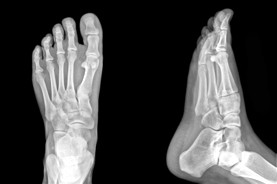

alberta plantar fascia

custom orthotics edmonton